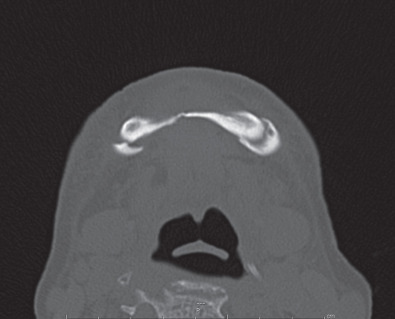

If maxillofacial trauma is suspected, radiographs will most likely be performed. Plain films of the maxillofacial region such as the mandible series, Waters view and submental vertex view are almost always now being replaced by the computed tomography (CT) scan. CT scans of the maxillofacial region give much better detail in a 3-dimensional aspect to assist the provider in diagnosing the injury and formulating a treatment plan. Occasionally, patients seen in the outpatient office will have an orthopantomogram (panorex) as a screening film for mandibular trauma. The orthopantomogram should have another radiograph in a second plane such as an AP film or CT scan to fully assess the injury. A CT scan is the optimal study to assess maxillary and upper face trauma. Additionally, the CT scan can be carried through the skull to assess bony and soft tissue injuries to the central nervous system and cervical spine ( Figs. 1.21.3–1.21.6 ).